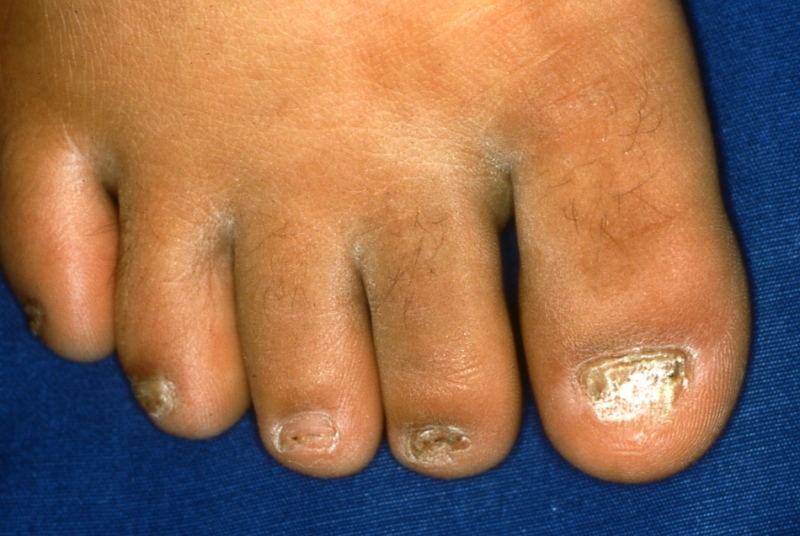

2.角化型足白癬

一見“ひび割れ”、“あかぎれ”と思わせますが、これも水虫です。

角化型足白癬(角質増殖型足白癬)(カチカチタイプの水虫)といいます。

カチカチタイプの水虫をはじめとする治りにくい水虫の、治療の第一選択は飲み薬です。